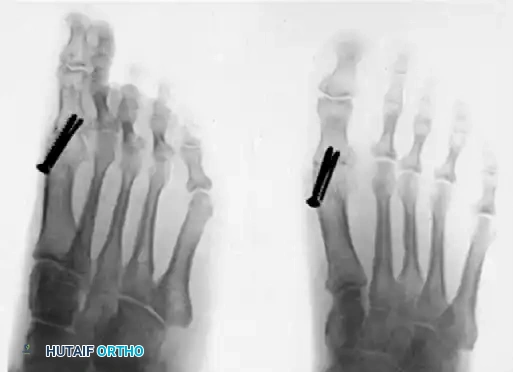

- Distraction Phase: At the 1-week postoperative clinic visit, sutures are removed, and baseline radiographs are obtained. The patient is instructed on the distraction protocol: turning the external fixator key one-quarter turn, four times a day. This equates to a distraction rate of exactly 1 mm per day.

- Goal: The distraction continues until the first and second metatarsals are of equal length, thereby restoring the normal windlass mechanism.

- Consolidation Phase: Once the desired length is achieved, distraction is halted. When radiographic evidence of consolidation (corticalization of the regenerate) is observed, partial weight bearing is permitted. The external fixator remains in place until full, robust consolidation is visible on multiple radiographic views. Following fixator removal, the patient may transition to full weight bearing and normal shoe wear as tolerated.